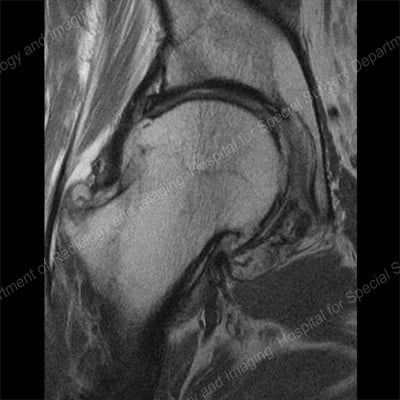

- MRI (magnetic resonance imaging): This can reveal subtle, early changes in bony and soft tissues of the joint.

MRI of the hip demonstrating osteoarthritis with large osteophytes around the femoral head.